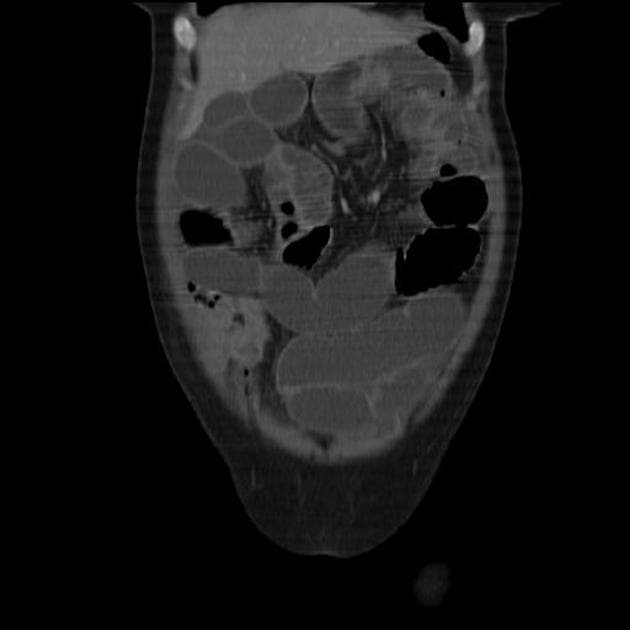

Coronal STIR

- Phù quanh khớp tăng tín hiệu (enhancing periarticular edema) ở khớp cùng chậu trái, lan đến cả phần màng hoạt dịch và phần sợi. Kèm theo một vùng nhỏ biến đổi mỡ (fatty metaplasia).

- Phù tăng tín hiệu tập trung tại phần sợi của khớp cùng chậu phải, kèm theo phù quanh khớp không tăng tín hiệu ở phần dưới của khớp.

- Không thấy phù quanh khớp hoặc biến đổi mỡ ở khớp cùng chậu phải.

Bệnh nhân này có tiền sử dương tính với HLA B27 và viêm cột sống dính khớp, các phát hiện trên cộng hưởng từ (MRI) gợi ý viêm khớp cùng chậu hai bên (bilateral sacroilitis). Tuy nhiên, viêm khớp cùng chậu biểu hiện không đối xứng, rõ rệt hơn ở bên trái; do bên phải có giải phẫu chuyển tiếp thắt lưng-xương cùng, có thể tồn tại thêm tình trạng rối loạn cơ học khớp cùng chậu, góp phần vào hình ảnh bất đối xứng này.

- "Viêm khớp cùng chậu hoạt động trong viêm cột sống dính khớp thường biểu hiện phù tủy xương quanh khớp đơn bên hoặc hai bên không đối xứng trên MRI."

- "Phù quanh khớp tăng tín hiệu trên MRI có tiêm thuốc cản quang là dấu hiệu hình ảnh chính của viêm hoạt động."